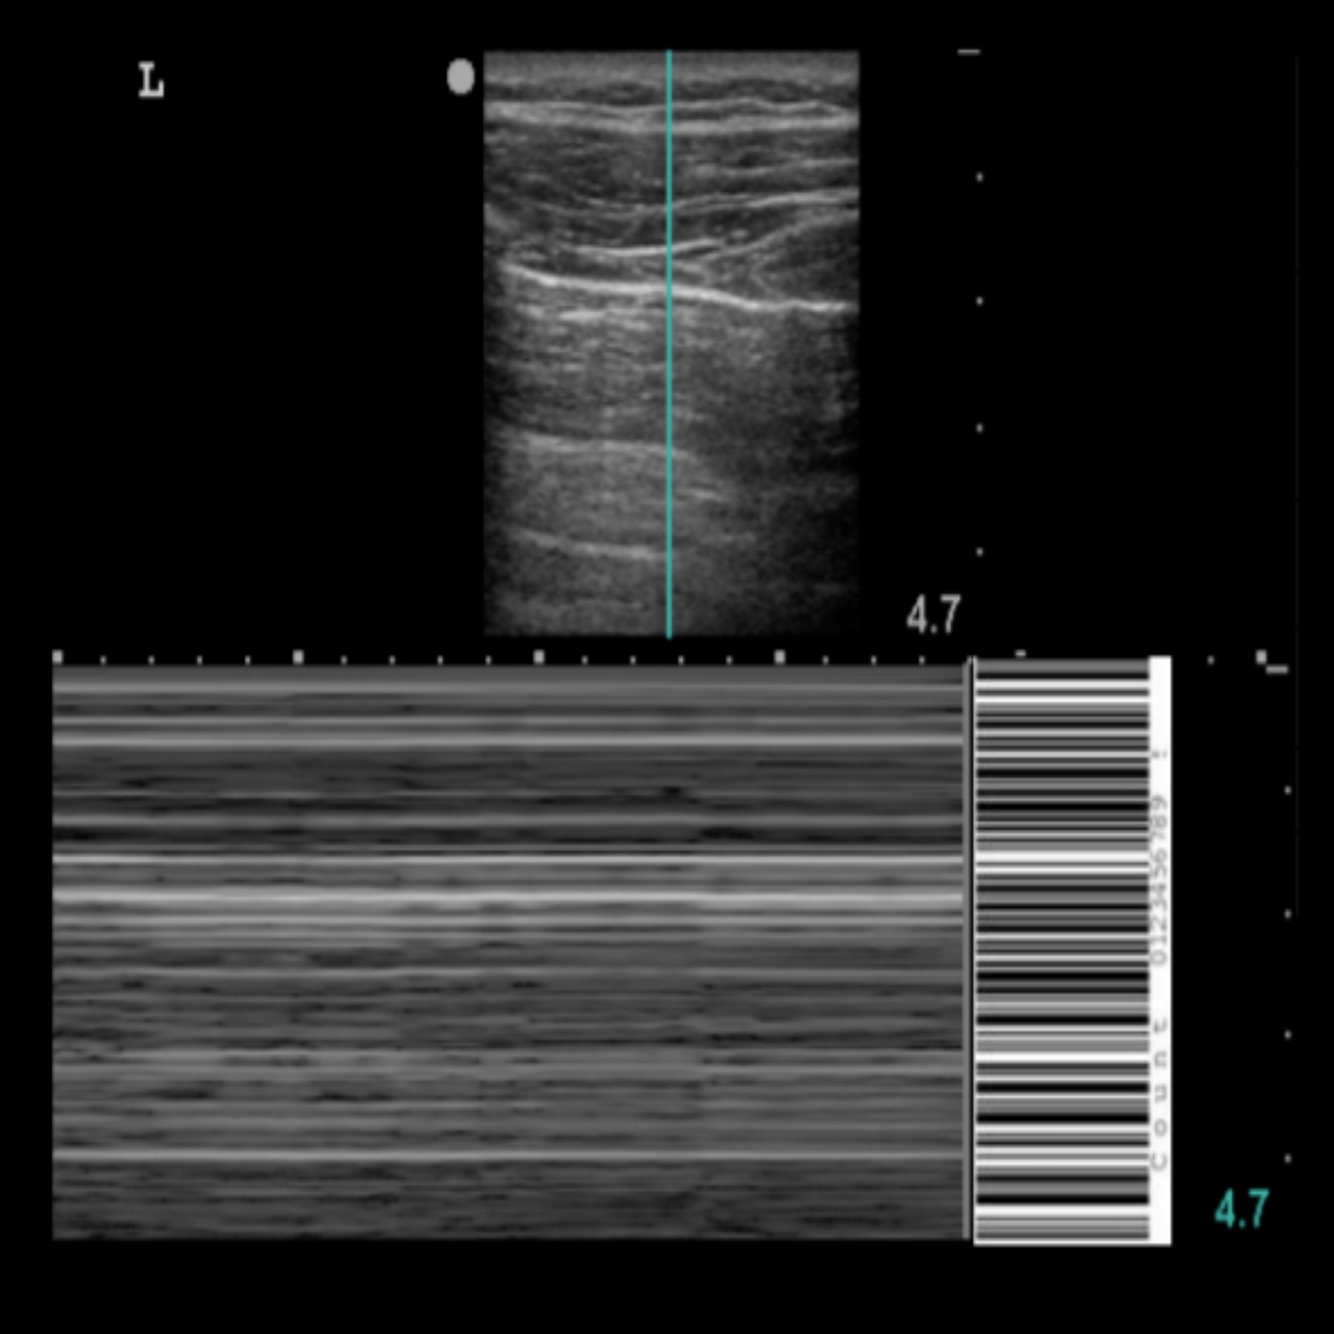

19

Q

POCUS PULMONAR: Qual o nome deste achado?

A

Ponto pulmonar

100% pneumotórax